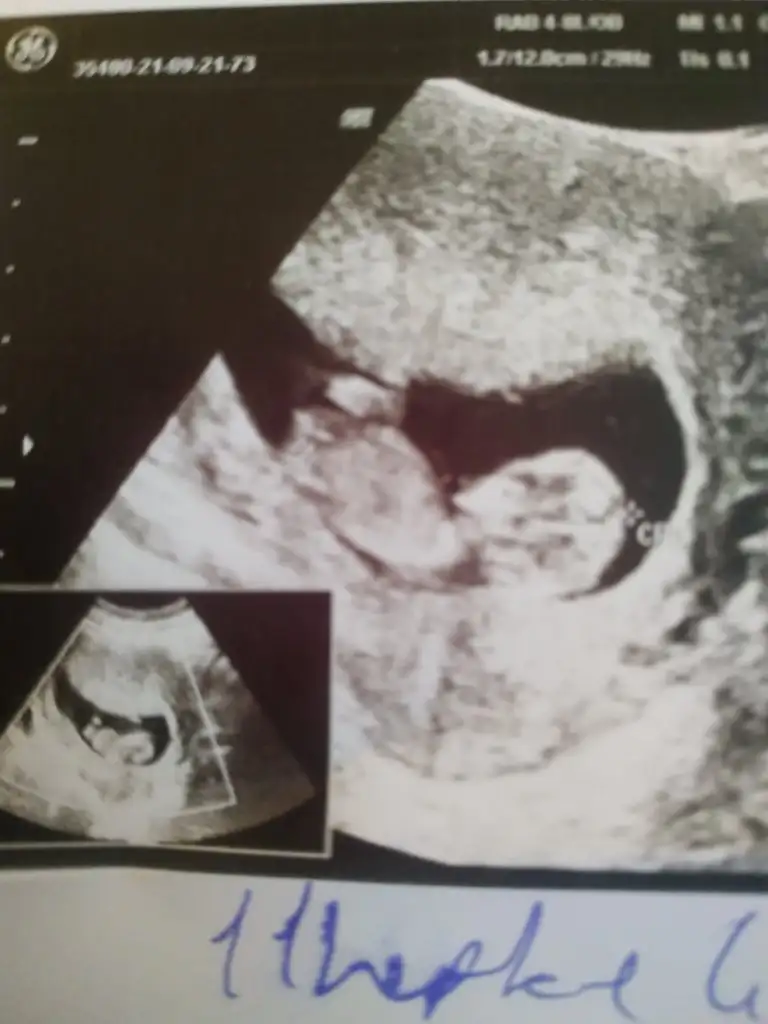

• d3cfddcb-c882-47e7-b969-b16103955a25.webp

d3cfddcb-c882-47e7-b969-b16103955a25.webp

19,9 KB · Görüntüleme: 106